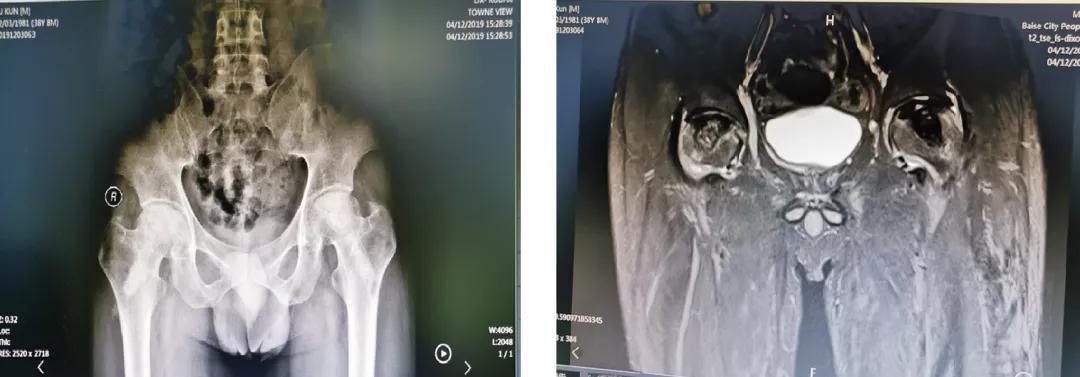

案例一

云南的苏先生今年38岁,出现双侧髋关节疼痛、活动受限1年多,被 明确 诊断为“双侧股骨头坏死”,坏死处于ARCO分期3期。在当地医院使用多种办法治疗,无明显效果,而后转到百色市人民医院关节与运动医学科。在患者及其家属强烈的保髋愿望下,科室选择了骨科机器人辅助下的微创保髋治疗,术后效果良好,患者满意。

术前辅助检查